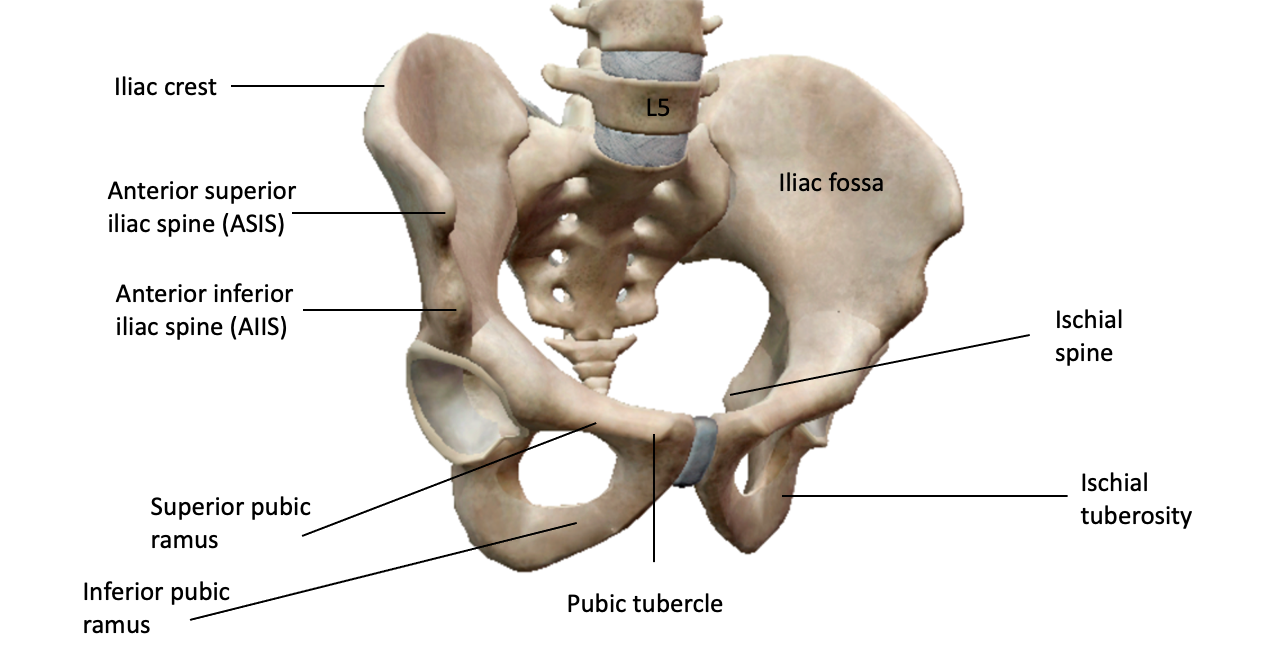

what is a synostosis fibrous joint? [1]

whats a bone with an example of a synostosis joint? [1]

what is a syndemosis fibrous joint? [1]

whats a bone with an example of where find a syndemosis joint? [1]

what is a gomphosis fibrous joint? [1]

whats a bone with an example of where find a gomphosis joint? [1]

what is a synostosis fibrous joint? [1]

At some sutures, the connective tissue will ossify and be converted into bone, causing the adjacent bones to fuse to each other (and make one big bone)

whats a bone with an example of a synostosis joint? [1]

frontal bone

what is a syndemosis fibrous joint? [1]

sheet of fibrous tissue between bones = interosseous membrane

whats a bone with an example of where find a syndemosis joint? [1]

between radius and ulnar / between tibia and fibula

what is a gomphosis fibrous joint? [1]

cone shaped peg fits into a socket

whats a bone with an example of where find a gomphosis joint? [1]

teeth